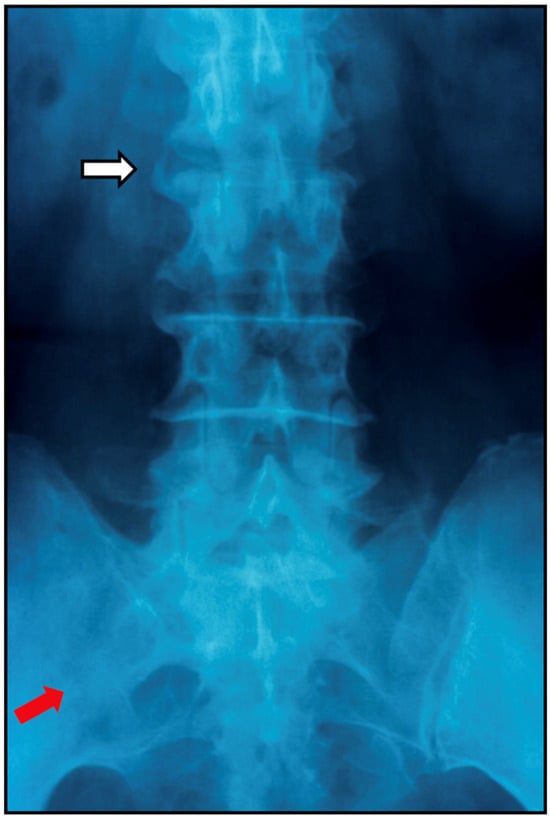

7.2.1. Plain Radiographs